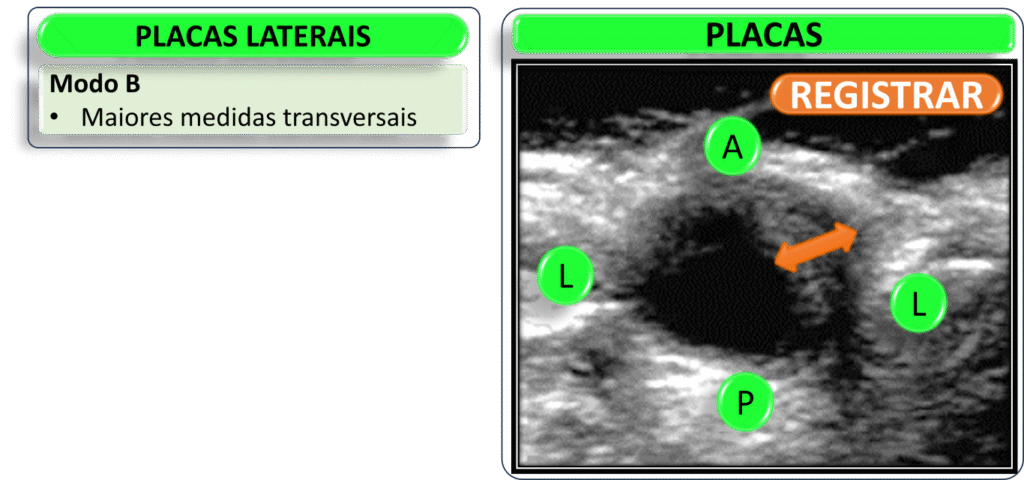

Imagens para registrar

O Doppler de carótidas é uma ferramenta fundamental para avaliar doenças arteriais.

Além da observação dinâmica em tempo real, é essencial registrar imagens que contenham as informações mínimas necessárias para um diagnóstico preciso.

Essas imagens devem incluir cortes longitudinais e transversais das artérias carótidas comuns, internas e externas. É importante destacar áreas de interesse, como placas, estenoses ou tortuosidades (kinks).